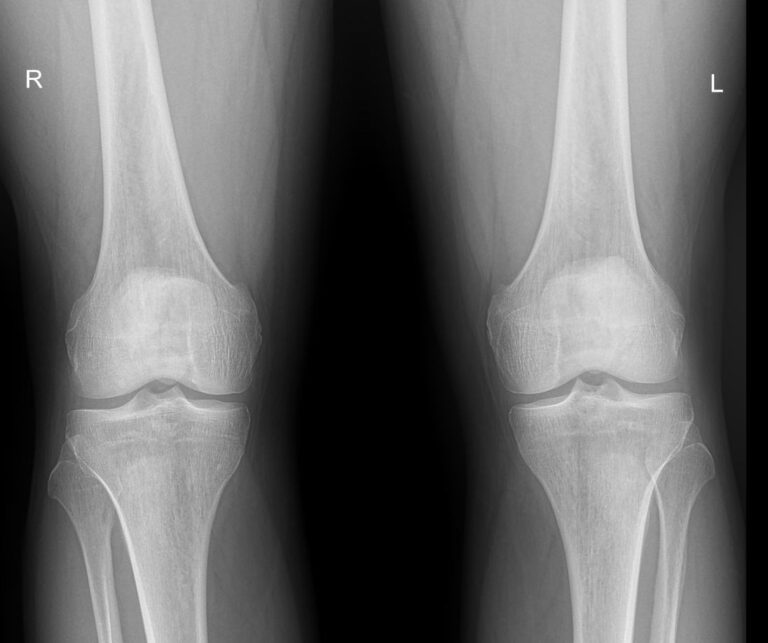

Назад Рентген обоих коленных суставов

Что покажет рентген обоих коленных суставов в одной проекции

В протоколе у каждого сустава описывается:

• Состояние мягких тканей;

• Суставная щель ― в норме, расширена, сужена, затемнена, имеет дополнительные включения;

• Состояние суставных  поверхностей и их соответствие друг другу ― несоответствие говорит о вывихе;

• Положение надколенника ― обычное или нет;

• Состояние костной ткани и надкостницы ― могут быть обнаружены участки разрежения, размягчения или других патологических процессов, а также свежие и сросшиеся переломы.